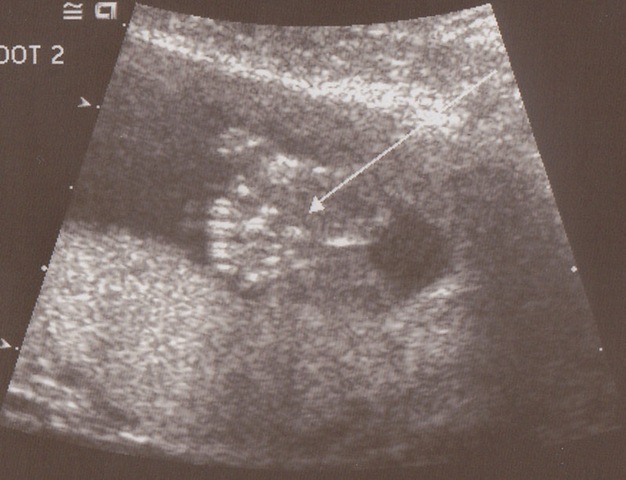

feet

Some feet!